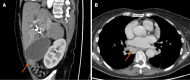

Case summary: A 70-year-old woman was referred to our center due to progressive fatigue, weight loss, abdominal pain, night sweats, and elevated liver enzymes. Magnetic resonance cholangiopancreatography and endoscopic retrograde cholangiopancreatography (ERCP) revealed proximal common hepatic duct and hilar biliary strictures extending bilaterally to lobular bile ducts. Although initial clinical, endoscopic and radiological signs were typical for hilar cholangiocarcinoma, histological examination showed no signs of malignancy. In total, 8 biopsies using different approaches were performed (several biopsies from dominant stricture during ERCP and direct cholangioscopy; ultrasound-guided liver biopsy; diagnostic laparoscopy with liver and lymph node biopsies). Histological examination revealed signs of IMT, and the final diagnosis of biliary IMT was stated. Although IMT is usually a benign disease, in our case, it was complicated. All pharmacological treatment measures were ineffective. The patient still needs permanent stenting, suffers from recurrent infections and mechanical jaundice. Despite that, the patient already survived 24 mo.